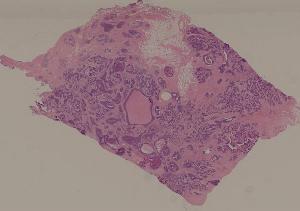

76. Acute pyelonephritis

77. Chronic pyelonephritis

41. Opportunistic infection in the lung

71. Acute transplant rejection of kidney

72. Lupus nephritis

36. Lymphoma

80. Invasive ductal cancer of the breast

84.Graves disease

93. Epidemic cerebrospinal meningitis

94. Encephalitis type B